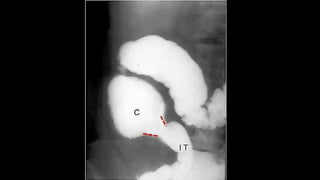

SIGNO DE LA MEDIA

LUNA O DEL MENISCO

• Signo de invaginación intestinal

en la radiografía simple de

abdomen.

• Corresponde a la semiluna de

gas intraluminal que queda

atrapado entre el asa

invaginada y el asa invaginante.

• En el enema opaco, se forma

por el bario que rellena el

colon hasta el ángulo opaco.

• El defecto de repleción

redondeado corresponde a la

cabeza de la invaginación.

Alrededor se acumula en bario

con forma semilunar.

SIGNO DE LAMEDIA LUNA O DEL MENISCO • Signo de invaginación intestinal en la radiografía simple de abdomen. • Corresponde a la semiluna de gas intraluminal que queda atrapado entre el asa invaginada y el asa invaginante.

• 7.

• En elenema opaco, se forma por el bario que rellena el colon hasta el ángulo opaco. • El defecto de repleción redondeado corresponde a la cabeza de la invaginación. Alrededor se acumula en bario con forma semilunar.